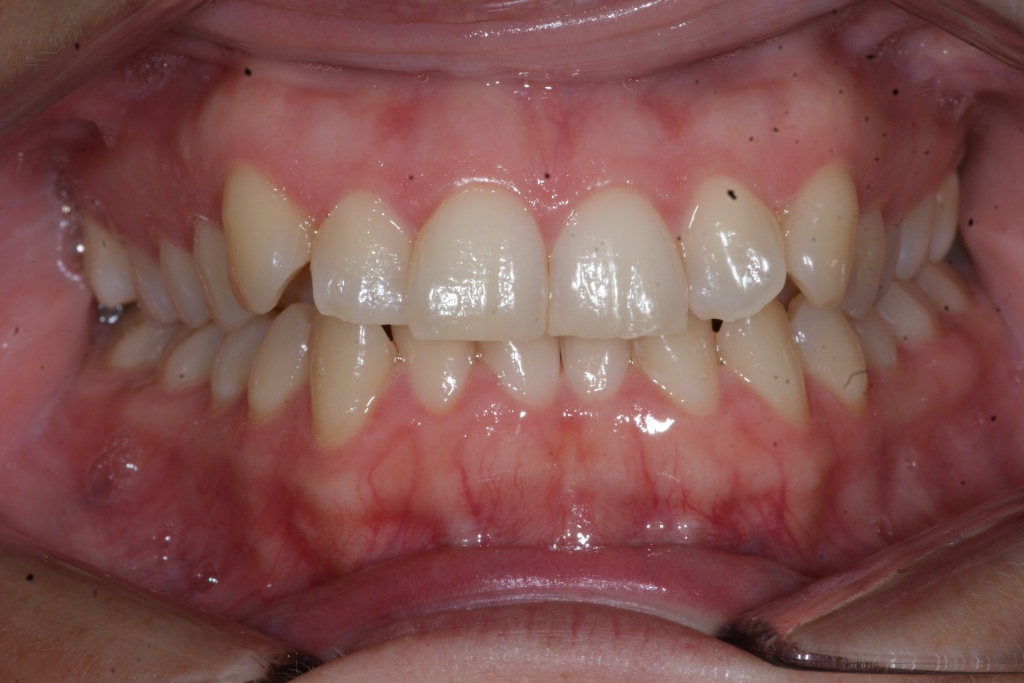

Correction d’une malocclusion de type Classe I, surplombs inadéquats et chevauchement modéré aux 2 arcades.  57 coquilles furent nécessaires pour améliorer ce sourire.  Traitement chez une adulte, réalisé en 15 mois.